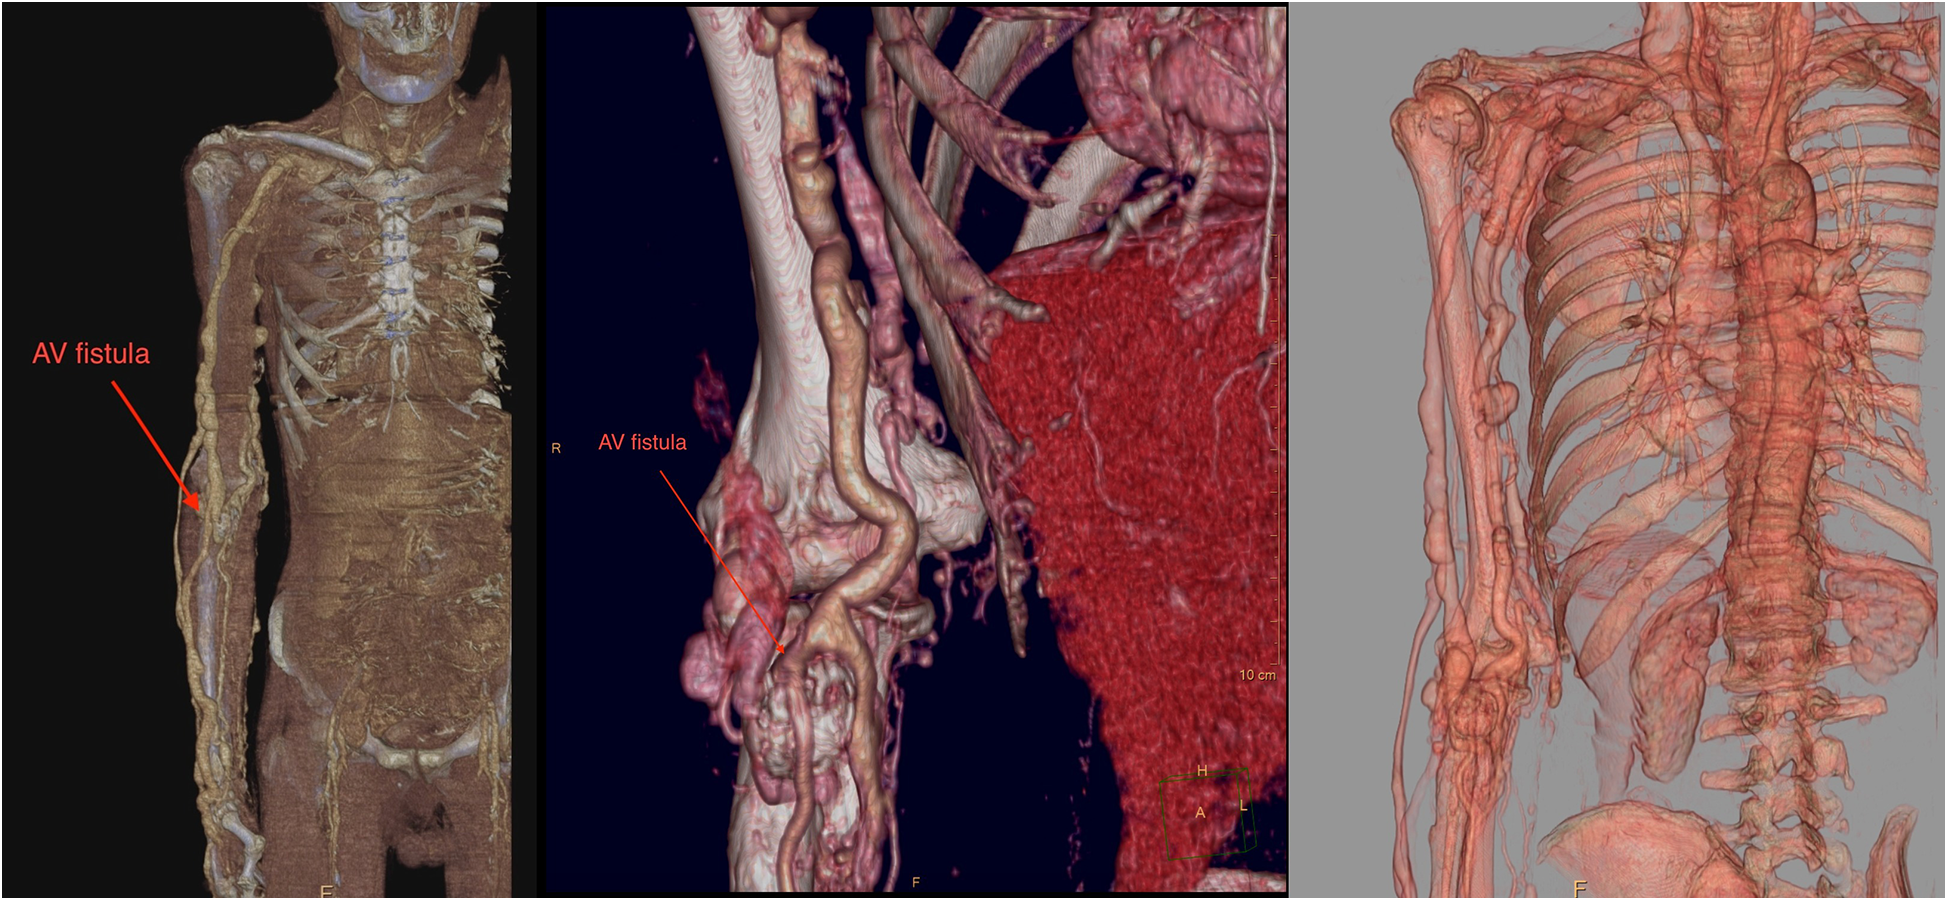

Upon admission to our institute, a CT scan of supra-aortic arteries and ascending and descending aorta was done. A CT scan of supra-aortic arteries revealed a diffusely dilated right axillar artery with a diameter of 19 mm, as well as a 21 × 15 mm aneurysm 46 mm from the vertebral artery's exit. CT scans of the ascending and descending aorta revealed a segmentally calcified ascending aorta with a diameter of 37 mm and arcus aortae with a diameter of 28 mm, as well as an aneurysm of abdominal aorta in the infrarenal segment, measuring 39 mm in diameter and 95 mm in length. CT scans reveal the existence of an arteriovenous fistula in the brachial artery (Figure 2). Doppler sonography of the right arm was performed, which was collaborated with CT findings of the same arm, the presence of an arteriovenous fistula (in the middle) on the inner side of the upper arm, and the presence of an arteriovenous fistula in the cubital fossa in an ulnar artery projection (Figure 3). Due to severe coronary disease, unprotected left main, and three-vessel disease, the heart team recommended surgical revascularization of the left and right system of coronary arteries. Standard on-pump CABG surgery in general anesthesia was done, with central cannulation of the aorta and through the right atrium. The anterograde infusion of cold blood del Nido cardioplegia stopped the heart. The surgical team decided on the use of a free mammary artery graft for LAD revascularization due to AV communication, and suspicion of steal syndrome. The right coronary artery and circumflex coronary artery were revascularized using a saphenous vein graft.

Figure 2

A contrast computer tomography of the upper arm revealed dilated axillary and brachial arteries with arteriovenous malformation (red arrow).